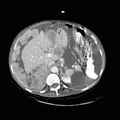

RADIOLOGY: ABDOMEN: Case# 33027: CARCINOMATOSIS. 80 year old female with history of umbilical herniorraphy and abdominal distention. 1) Large amount of ascites with multiple peritoneal based masses as described above. The appearance is consistent with peritoneal carcinomatosis from an as yet undetermined source. The differential diagnosis would include ovarian carcinoma, adenocarcinoma of the gastrointestinal tract, carcinoma of the breast, and renal cell carcinoma. There is apparent metastasis to the umbilical hernia site as well as to a 2 cm right inguinal node. 2) Small bilateral pleural effusions, right greater than left. 3) Simple left renal cyst.